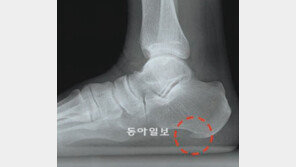

발바닥의 질긴 섬유조직(근막)에 염증이 생기면 발을 디딜 때마다 불편하다. 걷기 힘들 정도로 발뒤꿈치에 심한 통증을 느낀다면 ‘발바닥 근막염’이라고 봐야 한다. 19일 건강보험심사평가원에 따르면 이런 환자는 2007년 4만1463명에서 지난해 10만6197명으로 5년간 2.6배로 늘었…